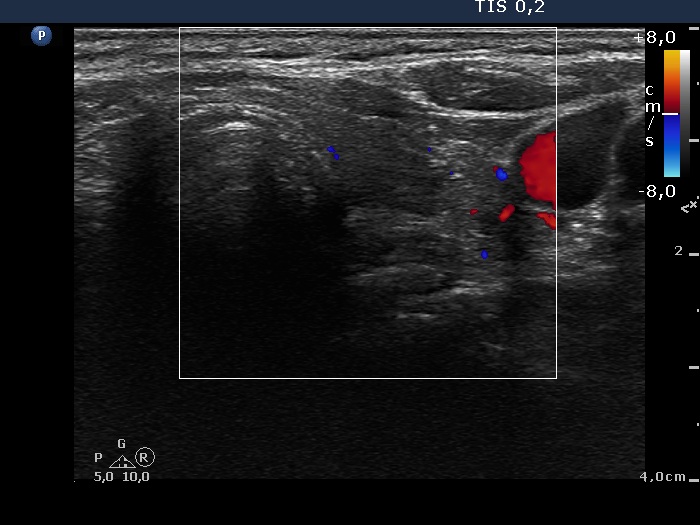

Ultrasonography: the right thyroid was echonormal while the left lobe contained moderately hypoechogenic areas with a 50% echogenicity index. There was a hypoechogenic mass lower and lateral to the right thyroid. The lesion did not present a regular hilum.